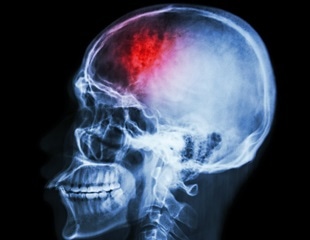

Dopamine in the brain influences movement, learning, motivation and sleep. In humans, problems with dopamine are linked to conditions like Parkinson's disease, depression and sleep disorders.